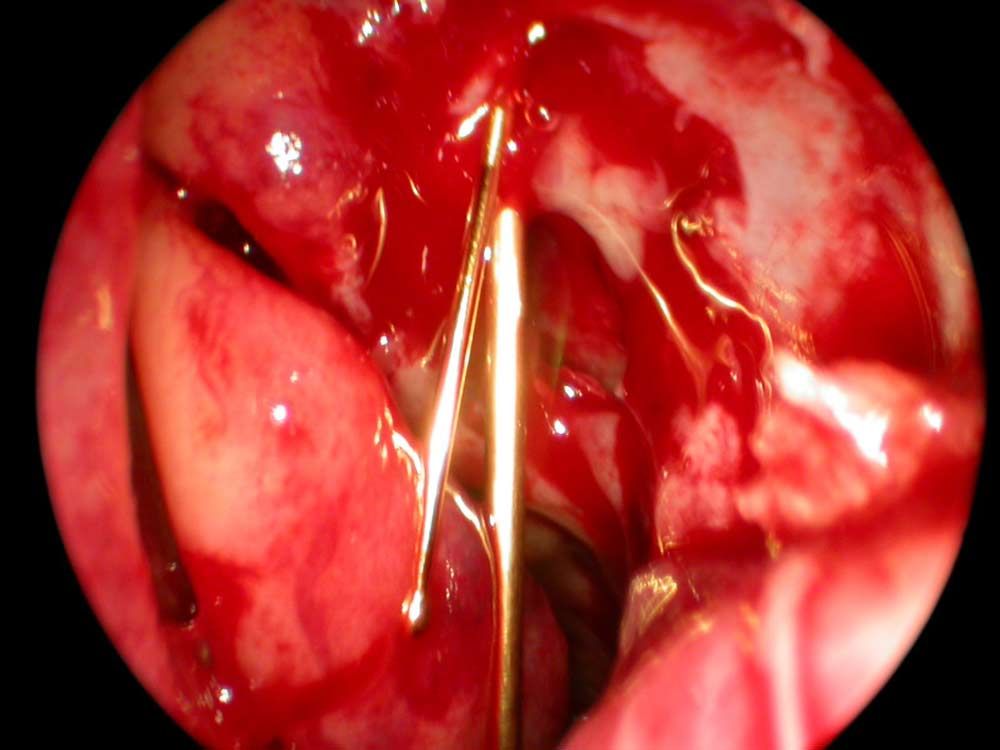

Tränenwegssonde in der Nase nach Eröffnen des Tränensacks